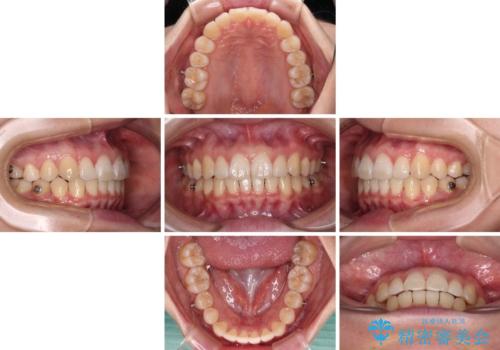

- 矯正装置

- インビザライン

- 上顎前歯の隙間を気にして来院された患者様です。

下顎前歯が上顎前歯に食い込むような咬み合わせにより、上顎前歯が開いてしまっていたため、咬合高径の挙上により突き上げを改善するよう、インビザラインにより矯正治療を行うこととしました。

咬合高径の挙上により上顎前歯の突出感も改善することができ、整った口元となりました。